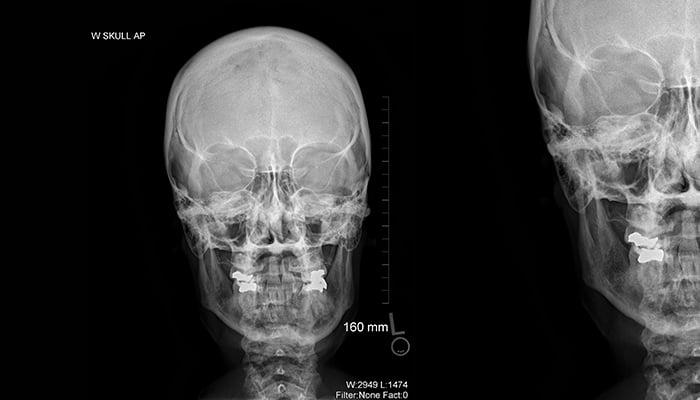

Skull X-ray

X-ray of a skull

Medical imaging exams allow health care professionals to look inside the human body to detect injury, diagnose disease or evaluate anatomical structures. Radiography, computed tomography, magnetic resonance, interventional radiography, sonography and nuclear medicine are a few examples of medical imaging techniques.